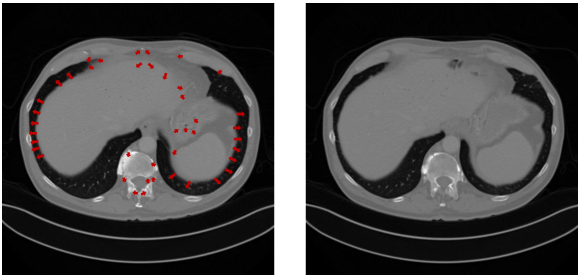

Following the equationย (4), we consider the question that whether the optical flow idea can be applied to 3D CT reconstruction. In practice, the brightness of adjacent CT images often has very tiny difference, due to the inherent continuity and structural integrity of human body. Therefore, we introduce the โlocal coherenceโ that indicates the correlation between adjacent images of a tissue. Namely, adjacent CT images often exhibit significant similarities within a certain local range along the vertical axis of the human body. Due to the local coherence, the noticeable variations observed in CT slices within the local range often occur at the edges of organs. We can substitute the temporal partial derivative by the vertical axial partial derivative in the equationย (4), where โzโ indicates the index of the vertical axis. As illustrated in Figures 1, the local coherence can be captured by the optical flow between adjacent CT slices.